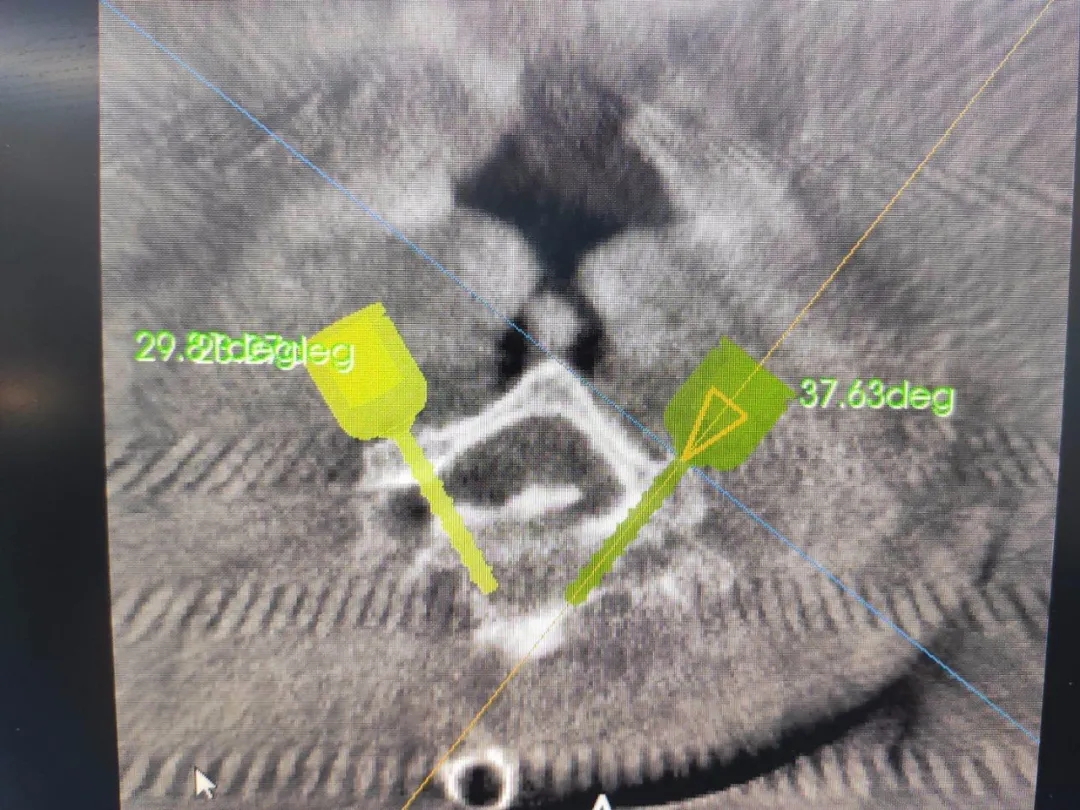

ÊõÖÐÔÚ°²ÅźÃÌå±í¶¨Î»ÒǺó£¬ £¬£¬£¬£¬µÐÊÖÊõ²¿Î»¾ÙÐÐÈýάɨÃ裬 £¬£¬£¬£¬ÍýÏë¾±7×µ¹­¸ùÂݶ¤Öö¤õè¾¶¡£¡£ ¡£¡£¡£¡£¡£

640.webp (2).jpg

640.webp (3).jpg

°´Éè¼Æ¾ÙÐÐÖÃÈëµ¼Õë

ÈýάÔÙ´ÎÑéÖ¤µ¼ÕëλÖ㬠£¬£¬£¬£¬Öõ¼¾«×¼